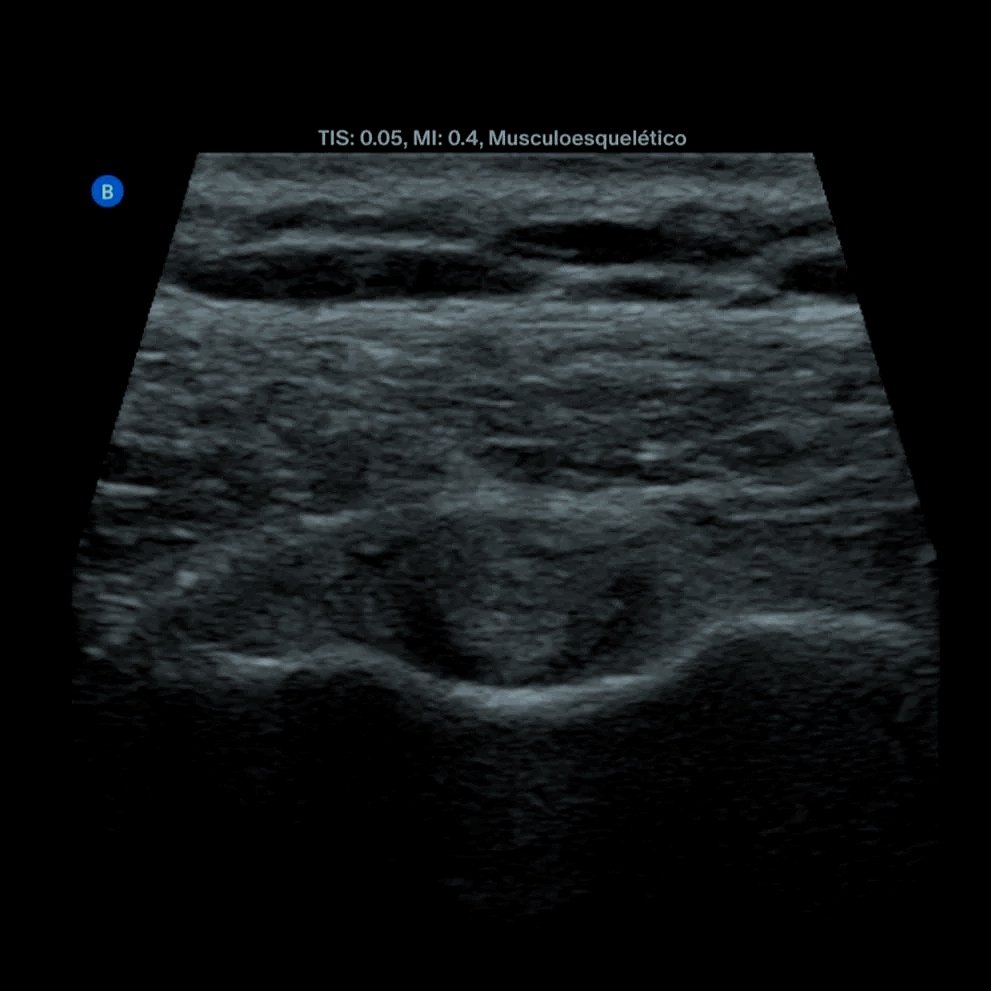

Imagen de una ecografía médica en escala de grises, mostrando estructuras internas del cuerpo humano.

Tendinitis de hombro